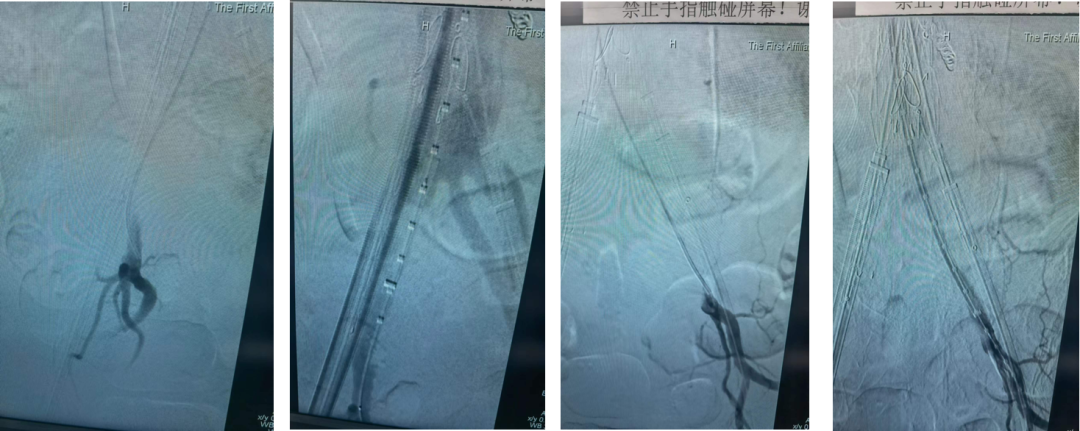

男性,63岁,腹主动脉瘤,双侧髂总动脉长度5mm左右,自制双侧内分支保留髂内

自制内分支,保留双侧髂内动脉,预置牵张导丝,方便重建

肾下引入腹主支架后,髂支引入改装后的内分支,利用牵张导丝,引导长鞘进入分支,超选重建髂内

瘤囊血栓化,髂支动脉通畅,患者预后良好

整体造影动脉瘤隔绝,髂内外通畅,术后1月随访,预后良好

自制内分支IBE保留双侧髂内动脉